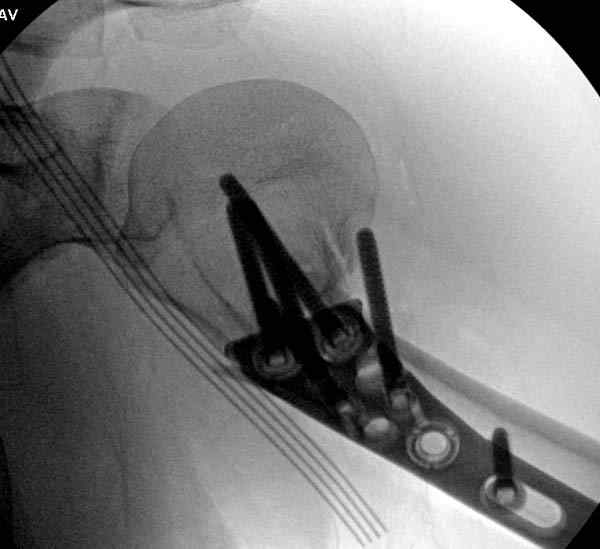

Здесь пример открытой репозиции 57 летнего с переломом плеча (1,2) смещение обнаружено на интероперационном снимке. При нормальной прямой проекция (3) угловое смещение обнаружили в аксиальной проекции (4)

После устранения смещения пластина установлена выше (5,6,7) и финальные снимки (8,9,10)

Подбор импланта тоже имеет значение, например многие импланты направлены для фиксации перелома без учета ротаторной манжетки. Предпочтительными являются низко сидящие полиаксиальные пластины, где верхние шурупы можно проводить под углом в 120 градусов. (11)

Пластина от Synthes или ее копии (надеюсь простят критику друзья из Деоста) считаются трудным из-за обширности доступа, особенно при установке верхне-заднего шурупа, где доступ надо расширять в верхнем отделе до ротаторной манжетки. Верхне сидящие импланты предназначены для проведения опоры (buttress) за бугристость плеча, но тогда приходится сталкиваться с подакромиальным импинжментом.